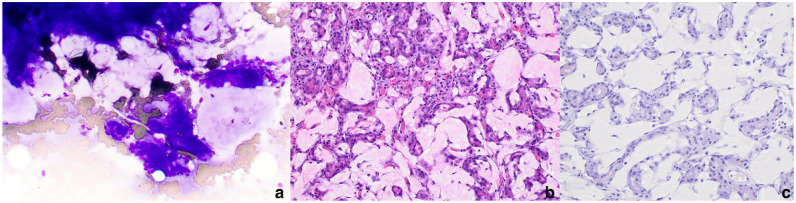

病例总结:一只6岁雌性家养短毛猫因腹胀和体重减轻而出现。腹部x光片和超声显示两个颅腹部肿块和另一个靠近空肠的肿块。颅腹部肿块的细胞学特征与外分泌胰腺组织一致。4个月后,复查腹部超声显示腹部肿块进行性增大和内侧髂淋巴结病。在剖腹探查时,两个腹部肿块与胰腺有关,并合并了供应肝脏、胰腺和脾脏的大血管。肿块不能切除,行切口活检。组织学特征可诊断为外分泌胰腺腺癌的透明化亚型。没有进行化疗。在最初发现腹部肿块后的28个多月里,这只猫还活着,据报道状况良好。相关性和新信息:据作者所知,这是猫胰腺腺癌透明化亚型的首次报道。这种亚型被认为在狗身上表现得不那么咄咄逼人,这个案例可能支持类似的,更懒惰的行为可能在猫身上看到。

Case summary: A 6-year-old female spayed domestic shorthair cat was presented for abdominal distension and weight loss. Abdominal radiographs and ultrasound revealed two cranial abdominal masses and another mass adjacent to the jejunum. Cytologic features of the cranial abdominal masses were consistent with exocrine pancreatic tissue. Four months later, a repeat abdominal ultrasound revealed progressive enlargement of the abdominal masses and medial iliac lymphadenopathy. On exploratory laparotomy, two abdominal masses were associated with the pancreas and incorporated large blood vessels supplying the liver, pancreas and spleen. The masses were non-resectable and incisional biopsies were obtained. The histologic features were diagnostic for a hyalinizing subtype of exocrine pancreatic adenocarcinoma. Chemotherapy was not pursued. Over 28 months after the initial detection of abdominal masses, the cat was still alive and reportedly doing well.